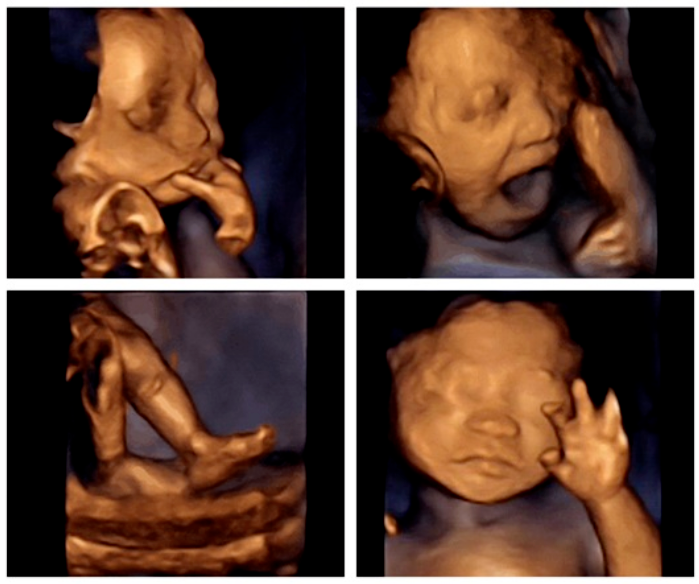

通过四维彩超我们可以发现

胎宝宝在"宫内"的生活可谓是多姿多彩

丰富的表情

像吸吮手指、打哈欠、吐舌头、捂着脸、微笑、皱眉......这些表情胎宝都会做,吃饱了还能吧唧下嘴,打个嗝。不开心了,还能皱着眉头发脾气,挥挥小拳头。